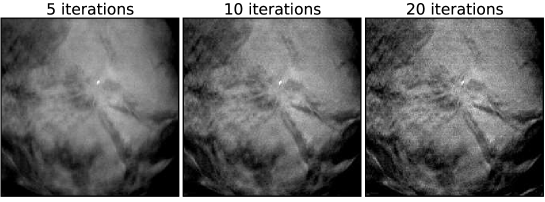

V.6 Case 3: spiculated mass in a dense breast

Finally, we present a case with a spiculated mass in dense breast tissue. It is precisely this type of case which DBT was developed for; by removing some of the interference of the overlapping structures such masses may be more conspicuous in DBT images than in standard mammographic projection imaging. The EM images are shown in Fig. 13, and the ASD-POCS images are shown in Figs. 14, 15, and 16. As with the previous mass case, there may be some advantage to image-reconstruction with ASD-POCS at low due to the fact that edges are enhanced. But the advantage is not as clear cut as it is with microcalcification imaging. Any advantage in mass imaging needs to be demonstrated by task-based image quality evaluation.

With this case, under-regularization, at large , tends to yield linear artifacts in the image. Actually, similar lines appear for the other cases in the first two iterations of ASD-POCS, but the quickly disappear and are gone by the fifth iteration. These lines, for the present case, are likely due to a slight system misalignment or patient motion. This case reveals the control afforded by the parameter in the ASD-POCS algorithm. It is easy to select a value of small enough to wash out the linear artifacts without severely blurring the underlying features of the image.